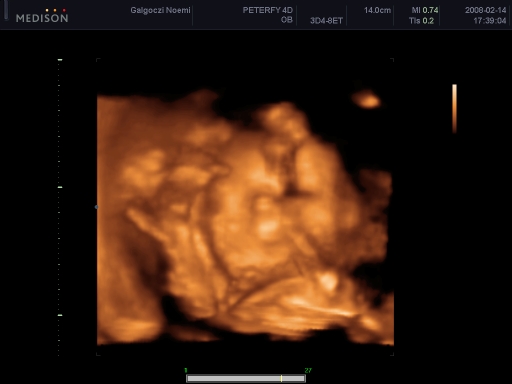

4 D-s ultrahang

Tegnap voltunk! Szuper volt, bár igaz, hogy csúszás volt, de vittem könyvet Bencének, és egész jól bírta!

Szóval:Csillához hasonlóan nekem is az AFP miatt kellett mennem, és tökéletesen egészséges. Borzasztóan ficánkolt! Bence pedig ott fekhetett mellettem, és együtt néztük! :)

Csak 2 D-n mutatta a kukiját, a másikon összezárta a lábát.

Boxolt, ivott a magzatvízből, pisilt, ásított, de szemből nem akarta megmutatni az arcát, mindig odakapta a kis kezét. Súlya: 356 g, fejecskéje 18 cm körben, pocija 15, combcsontja 3,3, ha jól emlékszem!

Összesen 27 db fényképet csináltak cd-n, ebből 1-et kaptunk nyomtatva is, és az egészről kaptunk egy dvd-t, ami 25-30 perc.

Kép

Itt a pofija látszik, a két keze, és bal oldalon felül a jobb talpacskája a feje tetején.

Levi ásít

Az egyik keze az álla alatt, a másikkal fogja a fejét

Olyan, mintha az alsón nem lenne orra! Én parázok egy kicsit, de állítólag csak valami árnyék miatt látszik így, és biztos kiszúrták volna!